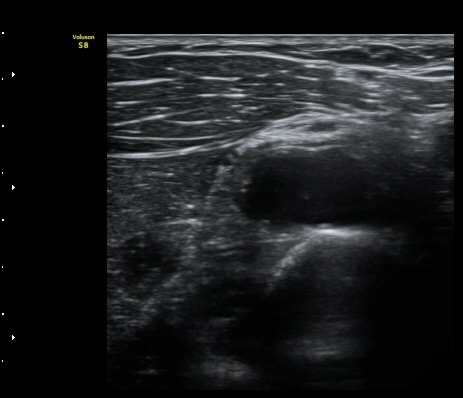

ŽÃËÀÚ¸¦ ¿ä°ñµÎ ºÎÀ§·Î À̵¿ÇÏ´Ï ¿ä°ñµÎ Ç¥Ãþ¿¡ Àú¿¡ÄÚ ³¶Á¾ÀÌ °üÂûµÇ°í ³¶Á¾ÀÇ ¿ÜÃø¿¡¼­

Èİñ°£½Å°æÀÌ ¾Ð¹ÚµÇ°í ÀÖ´Ù(±×¸² 2).